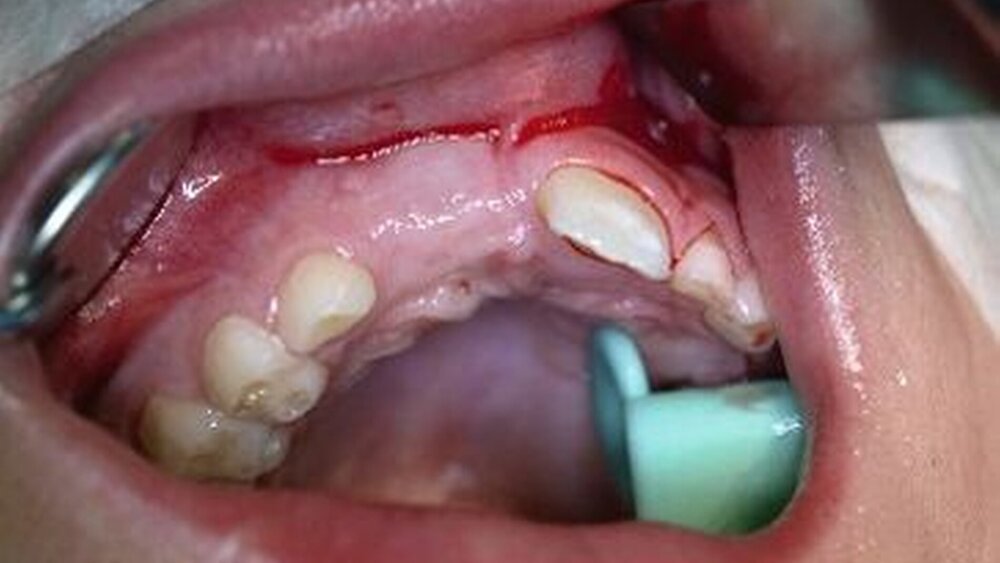

Klinisch findet sich neben häufigen, meist vertikalen Schleimhauteinrissen gegebenenfalls eine tastbare Stufenbildung (Abbildung 6). Dislozierte Alveolarfortsatzfrakturen gehen in der Regel mit einer Okklusionsstörung einher, die Sensibilität der betroffenen Zähne geht dabei häufig verloren. Die Therapie der Alveolarfortsatzfrakturen weist einige Besonderheiten auf, die in der entsprechenden Empfehlung der Leitlinie aufgeführt sind.